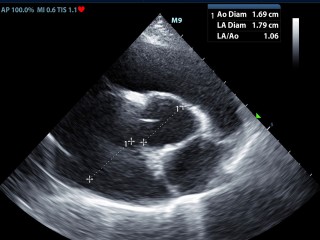

Echografie hart

Toen onze oude echoapparaat vervangen moest worden hebben we ervoor gekozen dat bij ons nieuwe echo apparaat het ook mogelijk moest zijn om echo onderzoeken van het hart te maken. Er moet dan o.a. doppler opzitten en je moet een ECG kunnen aansluiten, ook zijn de eisen voor de kwaliteit veel hoger. Onze nieuwe Mindray M9 voldoet aan deze eisen en heeft een zeer gevoelige en nauwkeurige echo detectie.

Dierenarts Rianne Compagner maakt de hartecho's, zij heeft diverse cursussen en nascholingen hiervoor gevolgd.

Het hart in beeld

Hieronder zie je een aantal foto's van het hart.